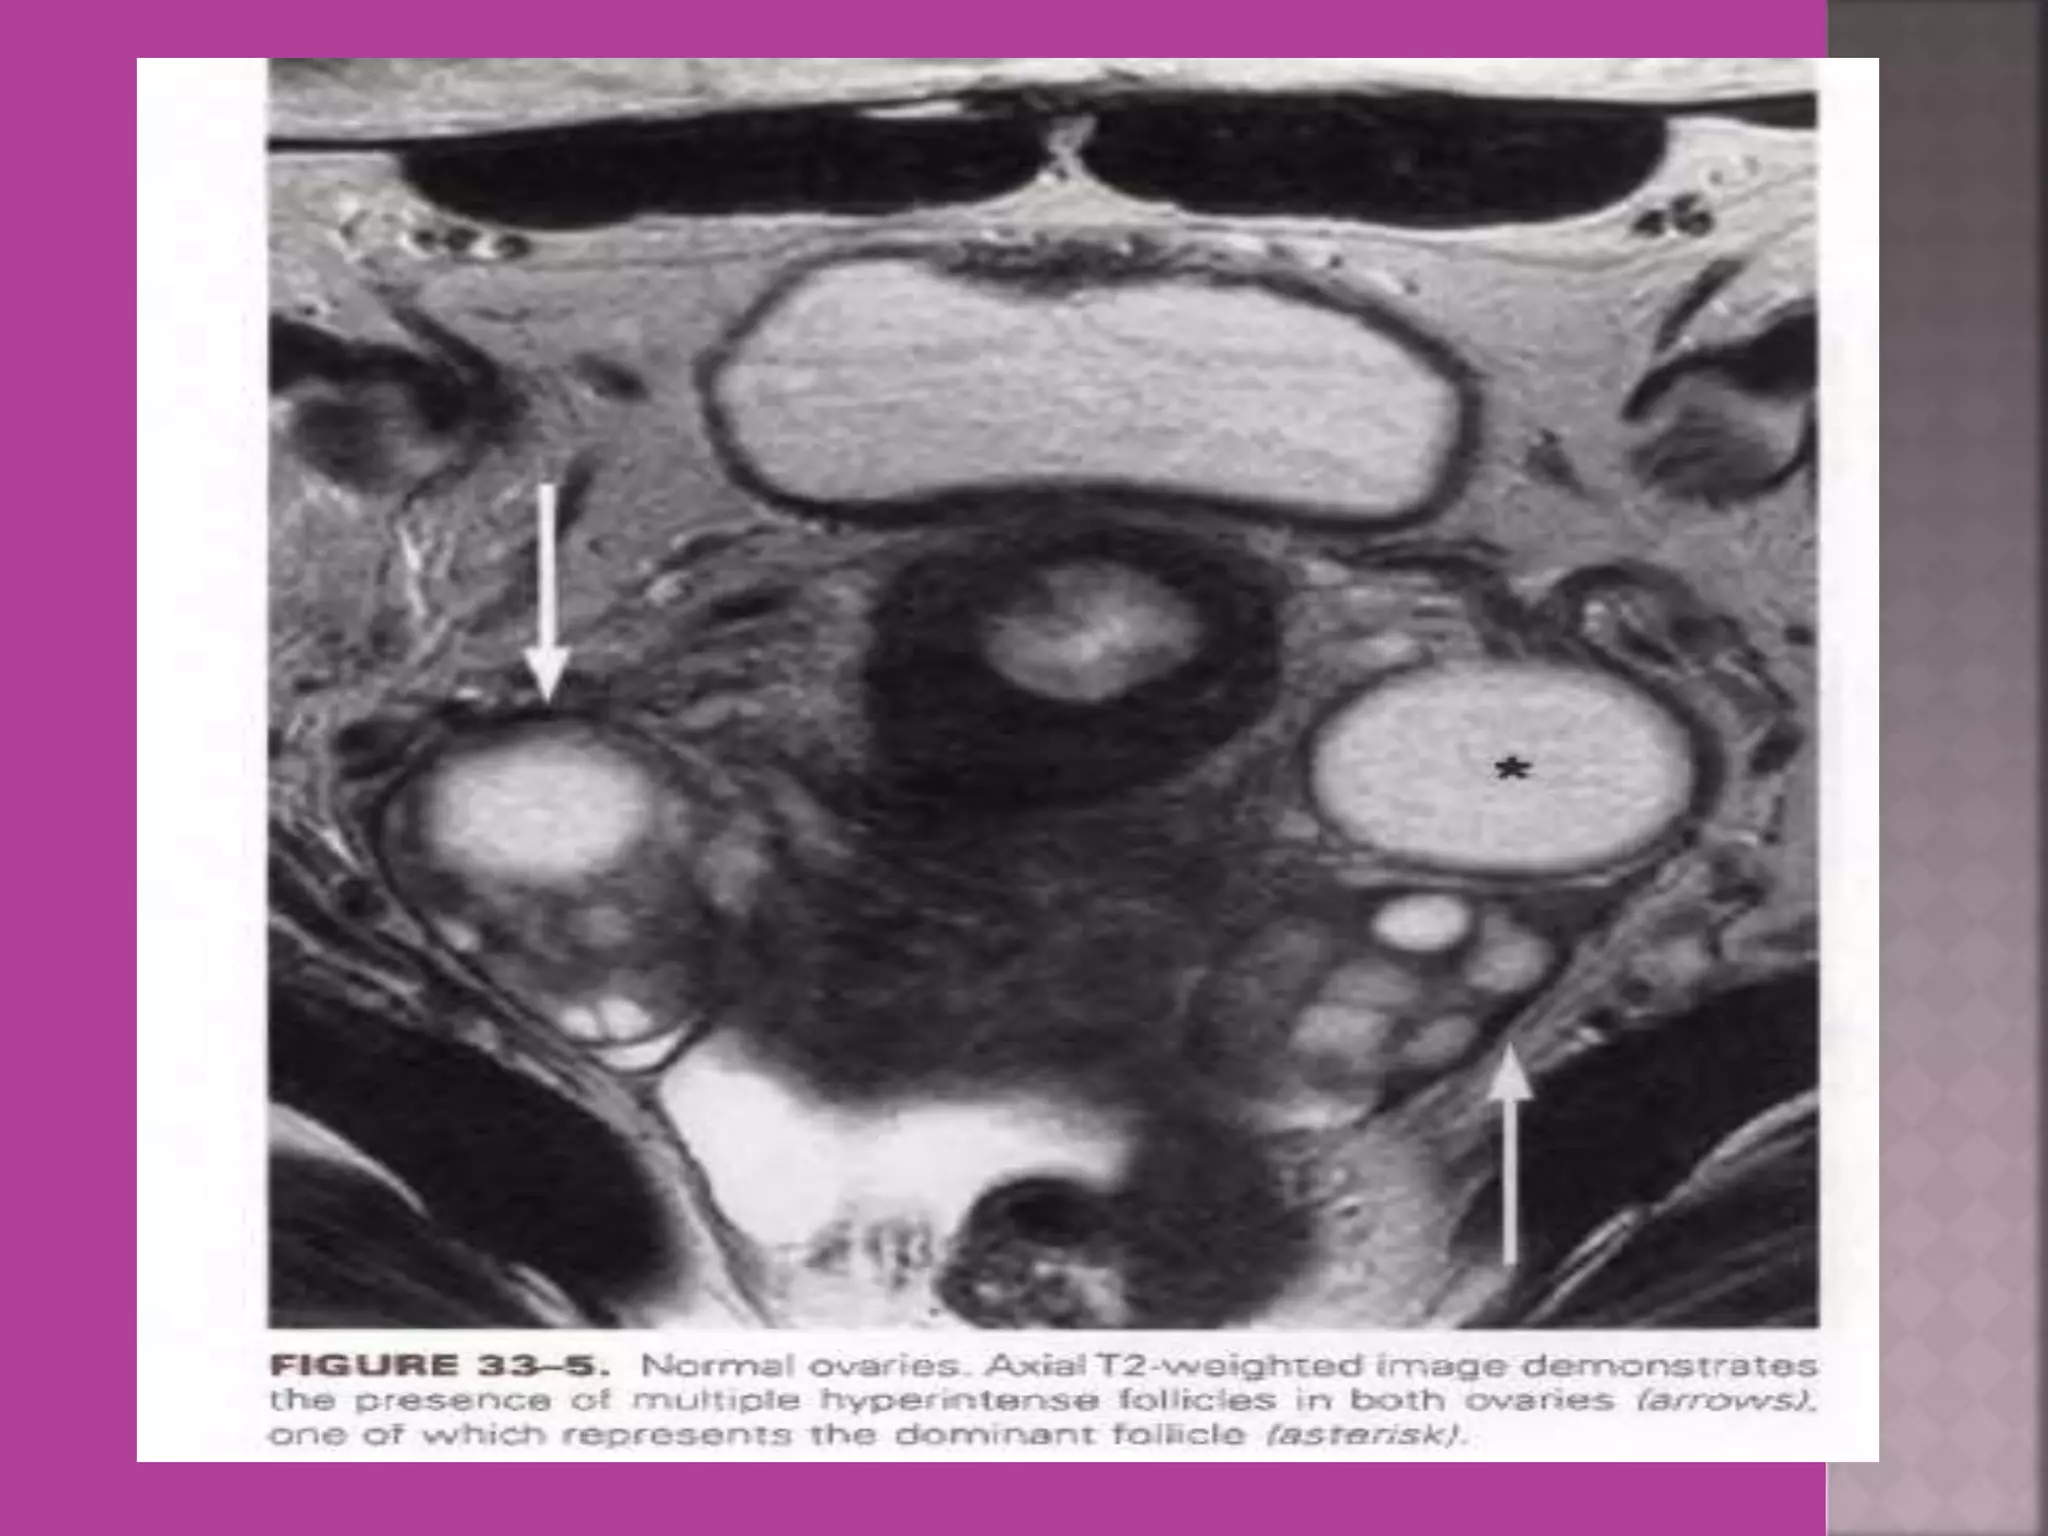

 Study of normal uterus and adnexa – with

aim to have clear image of normal

myometrium, endometrium , ovary and

follicles within the ovary.

 Study ofnormal uterus and adnexa – with aim to have clear image of normal myometrium, endometrium , ovary and follicles within the ovary.  Myoma—to differentiate myoma from adenomyoma.localization of myoma—sub serous/ intra mural or sub mucous.  Adenomyosis---accurate diagnosis.  Congenital uterovaginal anomalies— bicornuate, septate,subseptate , unicornuate, didelphys ,rudimentary horn and vaginal atrasia etc